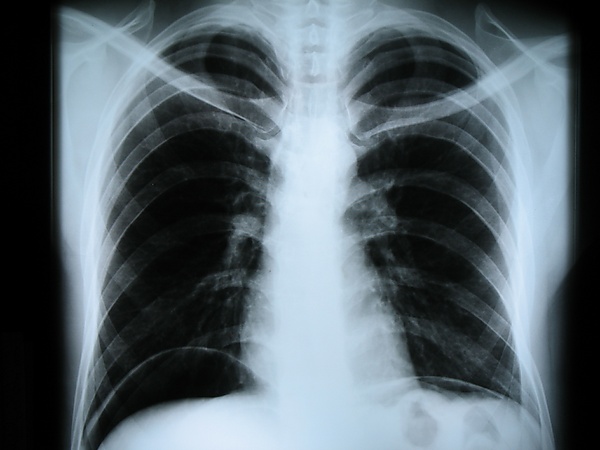

Наиболее часто термин относится к медицинскому неинвазивному исследованию, основанному на получении суммарного проекционного изображения анатомических структур организма посредством прохождения через них рентгеновских лучей и регистрации степени ослабления рентгеновского излучения.

Сейчас рентген грудной клетки часто используется для диагностики заболеваний, вызванных инфекциями лёгких. Однако этот метод оказался малоэффективен для обнаружения ранних стадий вирусных пневмоний, вызванных COVID-19.

Американские исследователи во главе с профессором Университета штата Огайо изучили рентгеновские снимки 630 пациентов с подтверждённым коронавирусом и выраженными симптомами. В 89 процентах случаев на рентгене не было заметно никаких отклонений, или они были незначительными. Практика врачей ГКБ №40 в посёлке Коммунарка, которые первыми приняли на себя удар пандемии в России, также подтвердила эти выводы. Тем не менее, на более поздних этапах с помощью рентгенографии можно получить точные и качественные результаты. Именно поэтому в текущей ситуации особенно актуальны портативные аппараты, которые можно применять в палатах пациентов в тяжёлом состоянии[3].

В настоящее время рентгенография остаётся основным методом диагностики поражений костно-суставной системы. Важную роль играет при обследовании лёгких, особенно в качестве скринингового метода. Методы контрастной рентгенографии позволяют оценить состояние внутреннего рельефа полых органов, распространённость свищевых ходов и др.